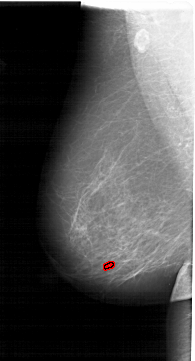

A_1513_1.LEFT_CC

LEFT_CC LINES 6586 PIXELS_PER_LINE 3421 BITS_PER_PIXEL 12 RESOLUTION 43.5 OVERLAY

FILE: A_1513_1.LEFT_CC.OVERLAY

TOTAL_ABNORMALITIES 1

ABNORMALITY 1

LESION_TYPE CALCIFICATION TYPE PLEOMORPHIC DISTRIBUTION CLUSTERED

ASSESSMENT 4

SUBTLETY 1

PATHOLOGY BENIGN

TOTAL_OUTLINES 1